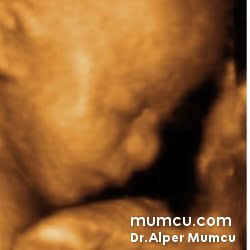

3 Boyutlu ultrason resimleri

Bu sayfadaki fotoğraflar degişik zamanlarda ve farklı hastalarda Dr. Alper Mumcu tarafından çekilmiştir.

11 haftalık gebelik